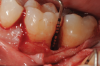

Fig 5. Surgical access and root preparation. The flaps were elevated after intrasulcular incisions were made and a releasing incision was done in the mesial aspect of tooth No. 19. The granulation tissue was removed.

Figure 5

Fig 6. 5-mm-deep distal intrabony defect at tooth No. 19.

Figure 6

In the present case, intrasulcular incisions were performed, followed by a releasing incision in the mesial aspect of tooth No. 19. A full-thickness flap was elevated in the buccal and lingual aspects (Figure 5 and Figure 6) using a minimally invasive periosteal elevator. The site was carefully managed to avoid salivary contamination.